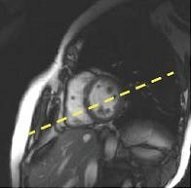

Figure 7. Short axis locations from a 4-chamber view